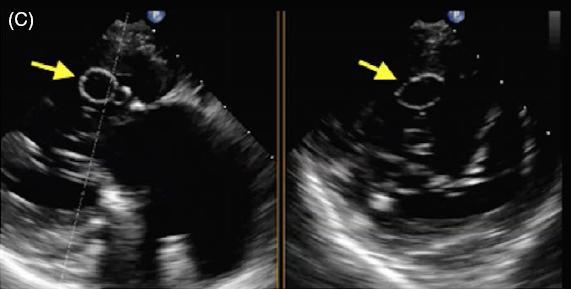

患者女,42 岁,以「急性视网膜动脉闭塞」病史就诊,既往无慢性疾病。经胸超声心动图检查发现二尖瓣后叶可见一囊状结构,可活动(图 A 和 B)。二维和实时三维经食管超声心动图检查显示一柔软的圆形结构附着于二尖瓣后叶,活动性良好(图 C ~ G)。主动脉弓、左心房、左心耳和左心室均正常。根据病变形态特征及超声表现,诊断为二尖瓣附瓣。其它影像学检查如 MRI、颈动脉多普勒超声均无异常。基于上述检查结果,考虑急性视网膜动脉闭塞为 AMVT 所致,建议外科手术切除二尖瓣附属组织,但是患者拒绝,选择随访观察。

图 C~F 二维经食管超声心动图显示一柔软的圆形结构附着于二尖瓣后叶,活动性良好